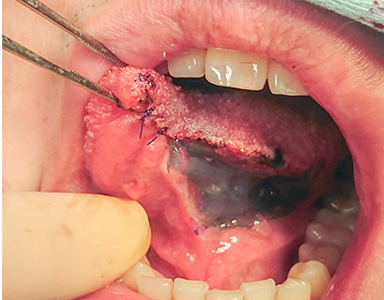

早期舌がんの治療(手術)の流れ

吸収性縫合補強材を貼付し手術終了